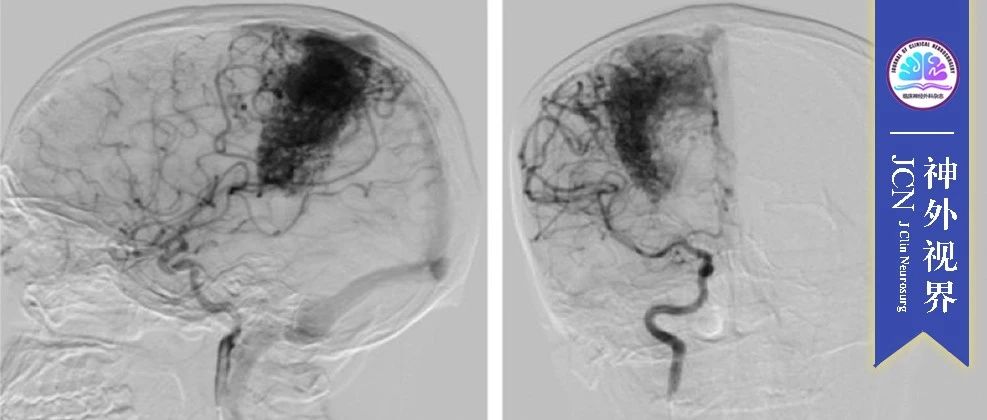

《JCN》神外视界|复杂脑动静脉畸形的显微外科手术治疗效果分析

刘建刚,副主任医师,副教授,硕士生导师,江苏省医学会神经外科分会颅底学组秘书,江苏省医师协会神经外科分会颅底学组秘书,江苏省神经外科质控中心秘书,苏州市第二届肿瘤生物治疗理事会理事。主持江苏省卫健委课题2项,苏州市课题2项,贵州省卫健委课题1项。获得江苏省卫健委新技术引进二等奖(排名第一)、江苏省卫健系统优秀党务工作者、苏州大学五四青年奖、贵州省援黔特别贡献奖、贵州省五一劳动奖章等荣誉。复杂脑动静脉畸形的显微外科手术...